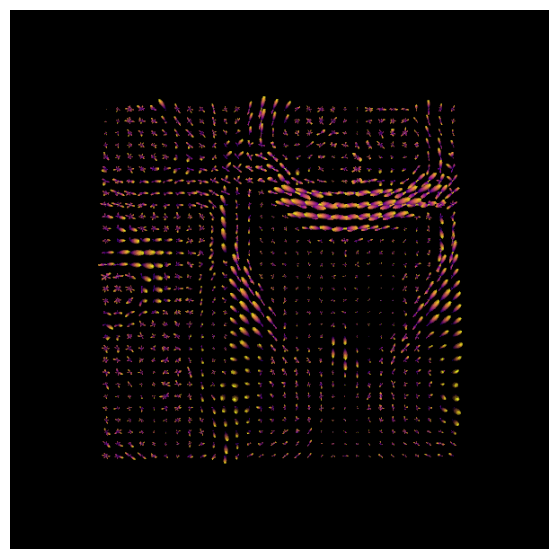

Now, we will use the python libraries DIPY and Matplotlib to visualize white matter FODs of an axial slice. However, we will also need to reconstruct the fiber orientation distribution function (fODF) with DIPY in two steps:

After estimating the response function, we can begin the deconvolution process by fitting the CSD model to the data.

# Set up the scene for visualization

scene = window.Scene()

# Fit the CSD model to the data

csd_model = ConstrainedSphericalDeconvModel(gtab_ap, response)

# Fit on a smaller portion of the data (optional for faster computation)

data_small = data[30:60, 40:70, 29:30]

csd_fit = csd_model.fit(data_small)

csd_odf = csd_fit.odf(default_sphere)

fodf_spheres = actor.odf_slicer(csd_odf, sphere=default_sphere,

scale=0.9, norm=False,

colormap='plasma')

scene.add(fodf_spheres)

csd_odfs = window.snapshot(

scene, fname=os.path.join(os.getcwd(), 'csd_odfs.png'), size=(600, 600),

offscreen=True)

fig, axes = plt.subplots(figsize=(7,7))

axes.imshow(csd_odfs, cmap="plasma")

axes.axis("off")

plt.show()

Using DIPY’s peaks_from_model, we can identify the peak directions (maxima) of the ODFs. We will then visualize the ODFs and their corresponding peaks in the same space.